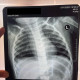

Alo dokter, izin konsul pasieen anak 1thn dgn keluhan batuk berdahak putih 2bln,demam 2 minggu dan pilek. Bb tidak turun,aktif,tidak ada riw kontak tb.

Untuk pemfis dalam batas normal

Uji tuberkulin blm dilakukan

Untuk hasil ro thorax seperti ini dok